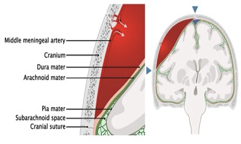

- 90% is arterial (middle meningeal artery)

- Biconvex, lens-shaped

- Commonly associated with skull fractures.